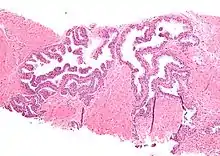

| Micrograph showing high-grade prostatic intraepithelial neoplasia. H&E stain. | |

High-grade prostatic intraepithelial neoplasia (HGPIN) is an abnormality of prostatic glands and believed to precede the development of prostate adenocarcinoma (the most common form of prostate cancer).[1][2]

It may be referred to simply as prostatic intraepithelial neoplasia (PIN). It is considered to be a pre-malignancy, or carcinoma in situ, of the prostatic glands.

Histology

HGPIN typically has one of four different histologic patterns:[2]

- tufted (fascicular patterning)

- micropapillary,

- cribriform and,

- flat.

Its cytologic features are that of prostatic adenocarcinoma:

- presence of nucleoli,

- increased nuclear-to-cytoplasmic ratio and,

- increased nuclear size.

Microscopically, PIN is a collection of irregular, atypical epithelial cells. The architecture of the glands and ducts remains normal. The epithelial cells proliferate and crowding results in a pseudo-multilayer appearance. They remain fully contained within a prostate acinus (the berry-shaped termination of a gland, where the secretion is produced) or duct. The latter can be demonstrated with special staining techniques (immunohistochemistry for cytokeratins) to identify the basal cells forming the supporting layer of the acinus. In prostate cancer, the abnormal cells spread beyond the boundaries of the acinus and form clusters without basal cells. In HGPIN, the basal cell layer is disrupted but present. PIN is primarily found in the peripheral zone of the prostate (75-80%), rarely in the transition zone (10-15%) and very rarely in the central zone (5%), a distribution that parallels the zonal distribution for prostate carcinoma.[6]